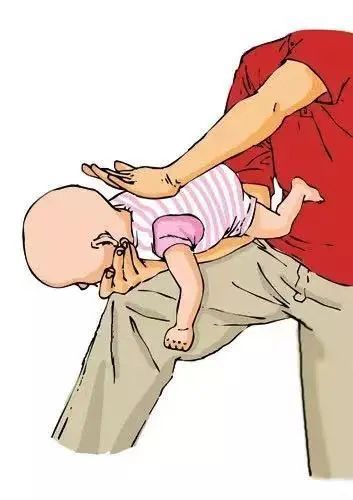

对于1岁以下婴幼儿,一只手托其面颊,使其面部朝下,头低于臀位,另一只手掌根部拍打其背部中央(两肩胛骨连线中点)5次,观察有无异物排出。若无异物排出,可让宝宝翻转使其面部朝上,一手固定宝宝,另一只手食指和中指按压孩子两乳头连线中点部位5次,观察有无异物排出。